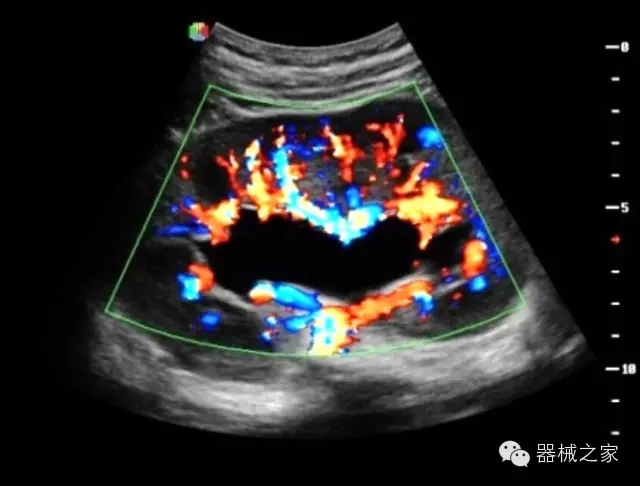

品牌:開立(SONOSCAPE)

深圳開立生物醫(yī)療科技股份有限公司作為中國(guó)民族醫(yī)療產(chǎn)業(yè)的優(yōu)秀引導(dǎo)者,自成立伊始,一直致力于臨床醫(yī)療設(shè)備的研發(fā)和制造,產(chǎn)品涵蓋醫(yī)用數(shù)字超聲診斷系統(tǒng)、電子內(nèi)窺鏡系統(tǒng)、全自動(dòng)五分類血液細(xì)胞分析儀以及自主研發(fā)的探頭群。

經(jīng)典產(chǎn)品:S8EXP

臨床圖片賞析